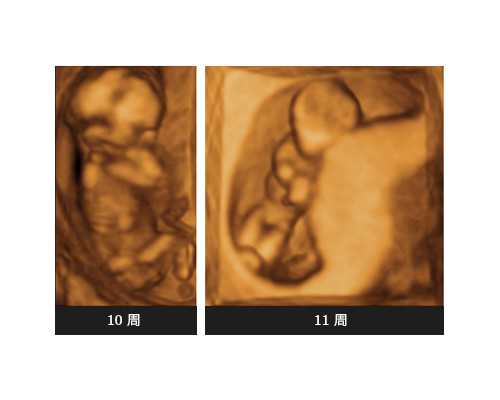

B超检查:这种检查最早需要怀孕5周以上,由B超检查中看到子宫内有圆形的光环即代表怀孕了,通过这种检查还可以排查宫外孕,对于怀孕的异常能及早发现。